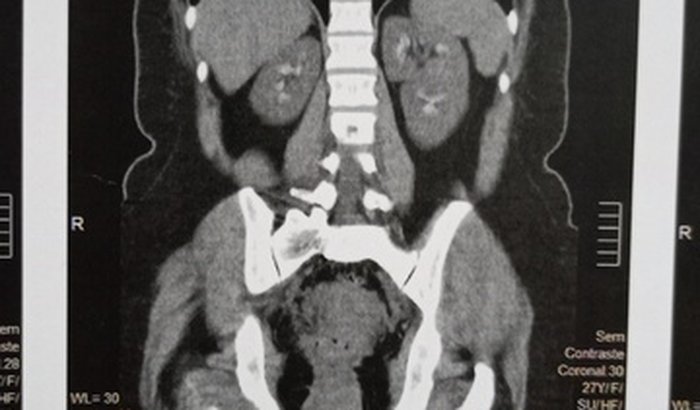

Eu sou Alice, tenho 27 anos venho aqui nessa vaquinha pedi pra vocês me ajudarem numa cirurgia de rins que preciso fazer urgente, pois tenho cálculos renais e neofraucalcinose (depósito de oxalato de cálcio ou fosfato de cálcio no parênquima ou túbulo renal) estou sofrendo com isso a quase um ano, e o pior de todo que todos os dias sinto dores horríveis que preciso ir no hospital tomar remédios na véia, venho aqui desesperada pedi a ajuda de vocês. Pois não tenho cond ções de realizar essa cirurgia, e pelo SUS está sendo difícil até encontrar médicos pra atendimento, por favor me ajude nesse obstáculos. qualquer valor simbólico á é de grande ajuda. Obrigada e fiquem com Deus 🙏